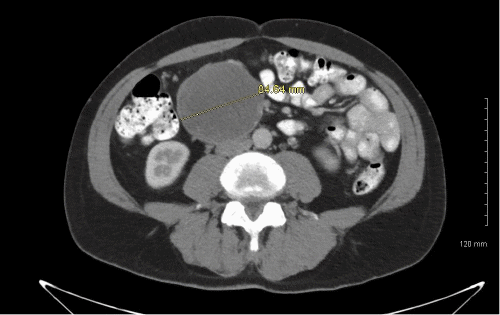

The patient is a 63-year-old male whose chief complaint was abdominal bloating for a couple of years. He denied any associated abdominal pain, nausea, vomiting, diarrhea, constipation, or any weight loss. His abdominal exam was significant for a palpable right upper quadrant mass. An abdominal ultrasound showed a right upper quadrant complex mass but no other abnormality. A follow-up CT confirmed a complex low-attenuation mass measuring 8.4 × 7.2 × 9.6 cm in the right abdomen abutting and compressing the head and the second and third portion of the duodenum, given the proximity of the mass to the duodenum and pancreas, pancreatic cancer was a suspected (Figure 1 and Figure 2). Therefore, an MRI and magnetic resonance cholangiopancreatography (MRCP) was done to evaluate and assess the anatomical delineation of the mass related to the pancreas and duodenum.

Figure 1. Axial CT Showing Large Intra-Abdominal Epidermoid Cyst. Published with Permission

The laparoscopic technique provides an effective method of surgical management in cases of pancreatic and splenic cystic lesions, avoiding the shortcomings of open surgery.5 However, laparoscopy is limited to the size of the cysts and the location, which may render minimally invasive surgery a risky option. In our case, the mass was a complex low-attenuation mass measuring 8.4 × 7.2 × 9.6 cm in the right abdomen abutting and compressing the head of the pancreas and the second and third portion of the duodenum (Figure 1 and Figure 2). In this case, laparotomy was deemed the best option to ensure complete and safe resection. There is always a concern for local recurrence of the cysts; the management and treatment are based on symptoms if they recur. These cysts are often benign, so chemotherapy or radiation is not warranted. However, there have been reports of these cysts having malignant transformation into squamous cell cancer.6 In our case, the patient underwent resection with the official pathology from the excisional biopsy, indicating the mass to be an epidermoid cyst with no malignancy noted in the tissue. Postoperatively, the patient's initial presenting symptoms had resolved entirely without any signs of recurrence after twelve months.